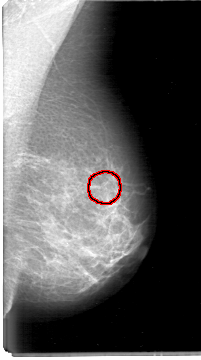

D_4054_1.LEFT_CC

LEFT_CC LINES 5326 PIXELS_PER_LINE 2971 BITS_PER_PIXEL 12 RESOLUTION 43.5 OVERLAY

FILE: D_4054_1.LEFT_CC.OVERLAY

TOTAL_ABNORMALITIES 1

ABNORMALITY 1

LESION_TYPE CALCIFICATION TYPE MILK_OF_CALCIUM DISTRIBUTION CLUSTERED

ASSESSMENT 0

SUBTLETY 3

PATHOLOGY BENIGN

TOTAL_OUTLINES 1

BOUNDARY